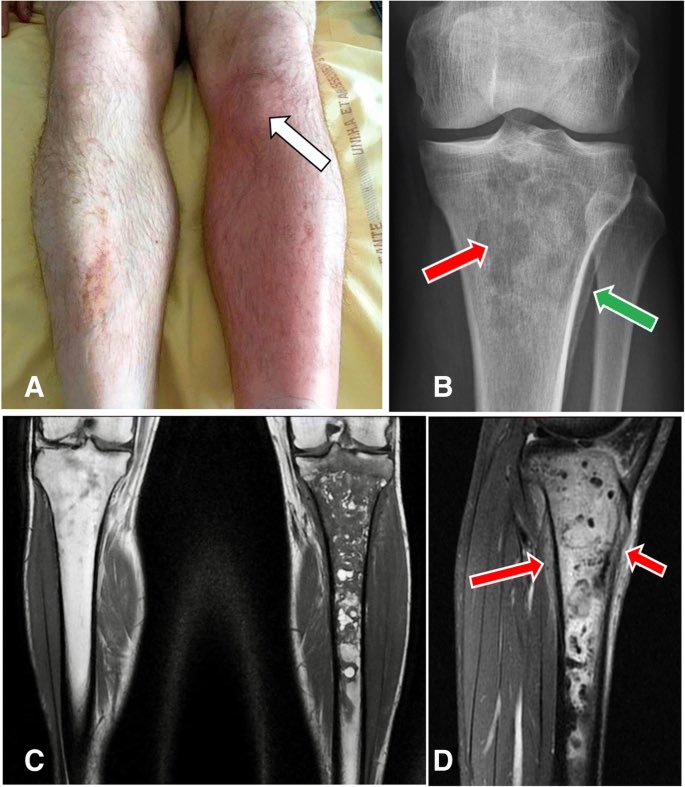

Deep Venous Thrombosis DVT

وهي اشهر مضاعفات كسور الجزء السفلي وكسور العمود الفقري، وتصير بسبب عدم حركة الجزء المكسور او تنويم المريض ف تبدأ تتكون خثرات دموية تسد شرايين مهمة ممكن تسبب جلطة دماغية او رئوية، ومن اهم علاماتها تورم البطة وسخونيتها والم عند تحريك الكاحل Homan's sign